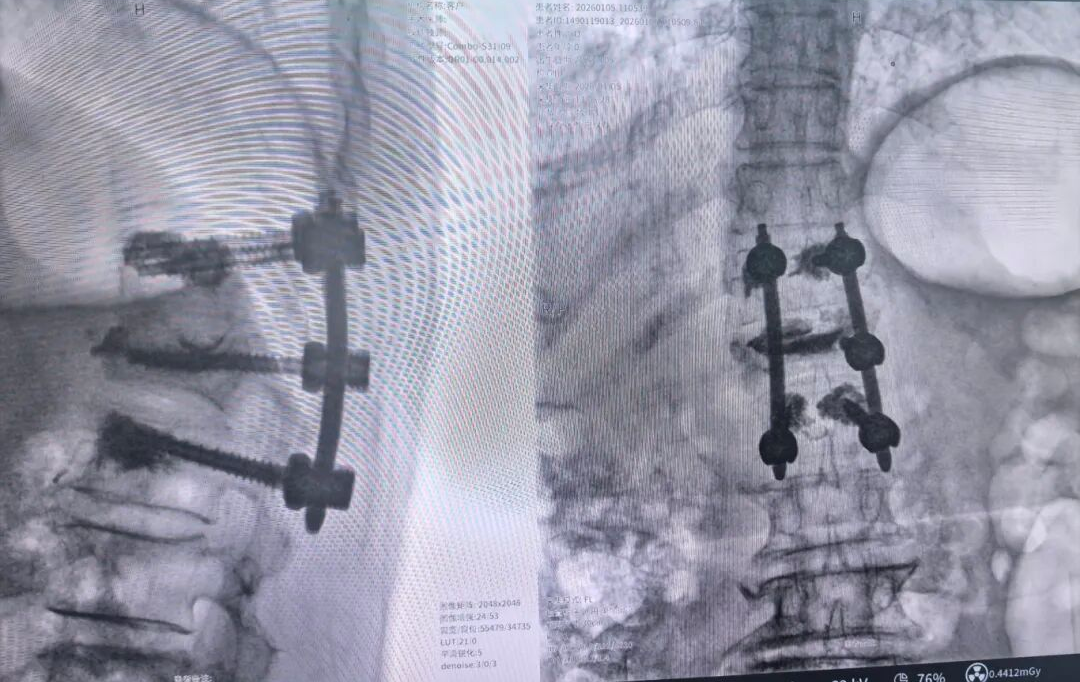

术后影像:

◆ 螺钉精准固定:仅通过6个8mm的微创切口,机器人机械臂自动调整角度,将6枚骨水泥强化螺钉精准植入T11-L1椎体,误差不足0.3mm;

术后1周复查CT显示,螺钉位置精准,骨水泥均匀分布,无椎管渗漏,椎管狭窄解除。